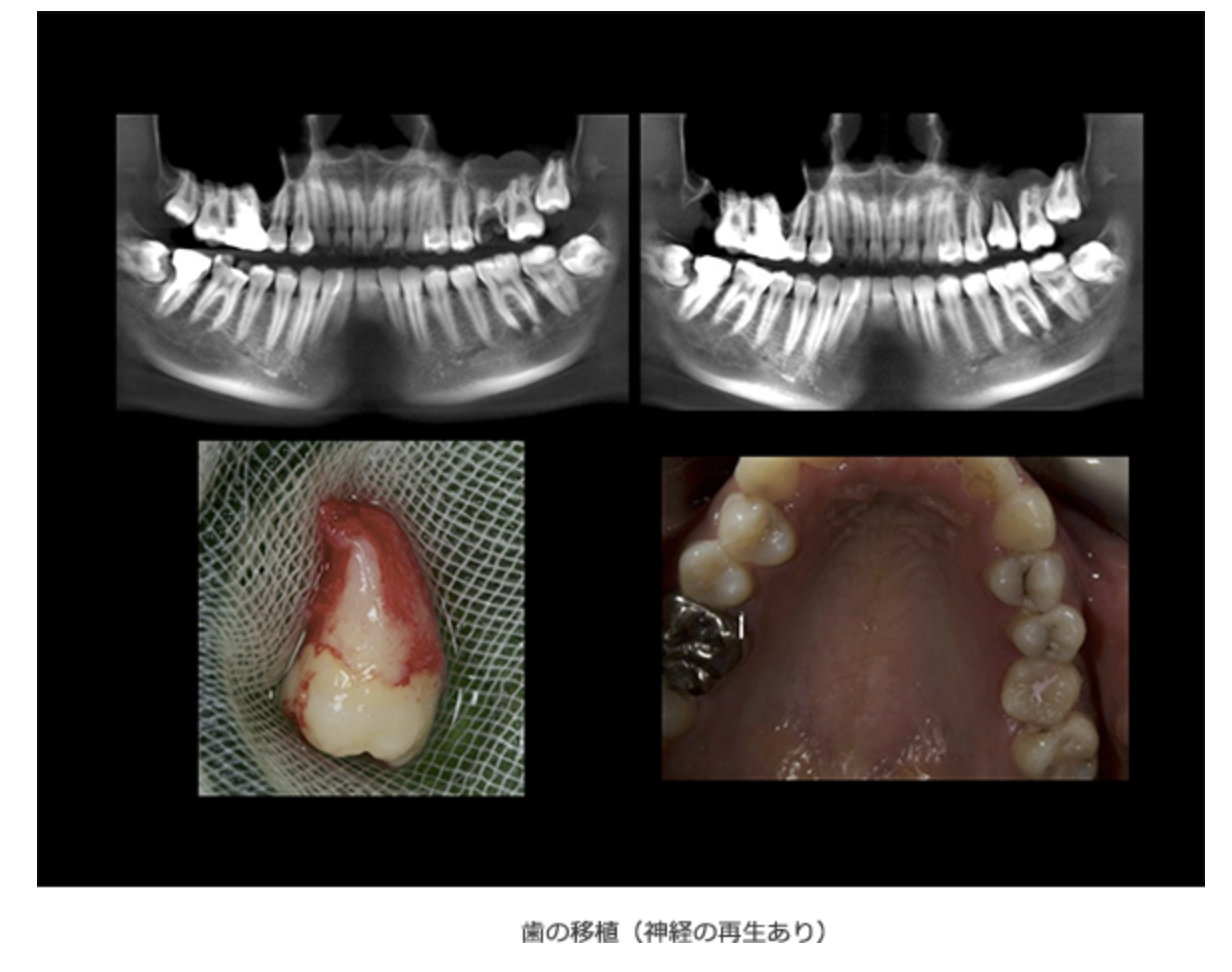

自分の歯を活かした自家歯牙移植治療

歯を失った場合の新しい選択肢として「自家歯牙移植」をご提案しています

アリーナデンタルクリニックでは、歯を失った場合の新しい選択肢として「自家歯牙移植」をご提案しています。自家歯牙移植とは、親知らずや不要な奥歯を別の位置に移植する方法で、インプラントやブリッジに代わる治療法として注目されています。この方法では患者様ご自身の歯を使用するため、自然な感覚で噛むことができ、歯根膜があることでインプラントと比較して繊細な噛み心地を感じやすいのが特徴です。

自家歯牙移植は高度な技術を必要とし、適応には条件がありますが、アリーナデンタルクリニックでは経験豊富な歯科医師が患者様の症例を丁寧に確認し、最適な診断の上で治療計画を立てています。他院でブリッジやインプラントを勧められた方にも、移植に適した親知らずや奥歯がある場合には、この治療を選択肢の一つとしてご案内しています。

ご自身の歯を活用することで、より自然な治療をご希望の方は、ぜひご相談ください。